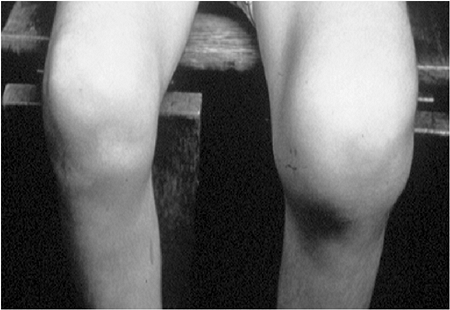

Figure 11.4 A:

A 16-month-old boy presented with a 3-week history of pain and swelling in all digits of both hands. He was treated initially as having dactylitis, and all but his left thumb swelling resolved. Physical examination revealed a fluctuant mass in the thenar eminence. Plain radiographs (B and C) revealed bone destruction in the left thumb metacarpal, as well as in both small finger metacarpals. Operative drainage of the abscess and corticotomy of the thumb metacarpal were performed. Cultures grew Escherchia coli. Four weeks of intravenous antibiotic therapy led to the resolution of symptoms and ultimate normalization of radiographs. |